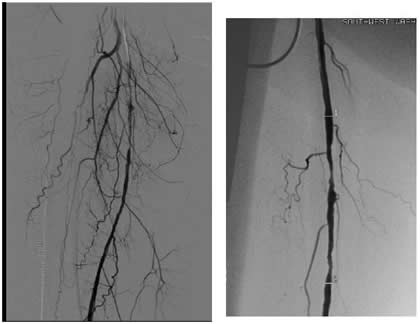

Case 2: A 74-year-old male with new onset severe claudication and threatened toes on the right side. An up-and-over wire was able to be advanced into the superficial femoral artery (but was totally occlusive). Cryoablation restored patency (Figure 2).